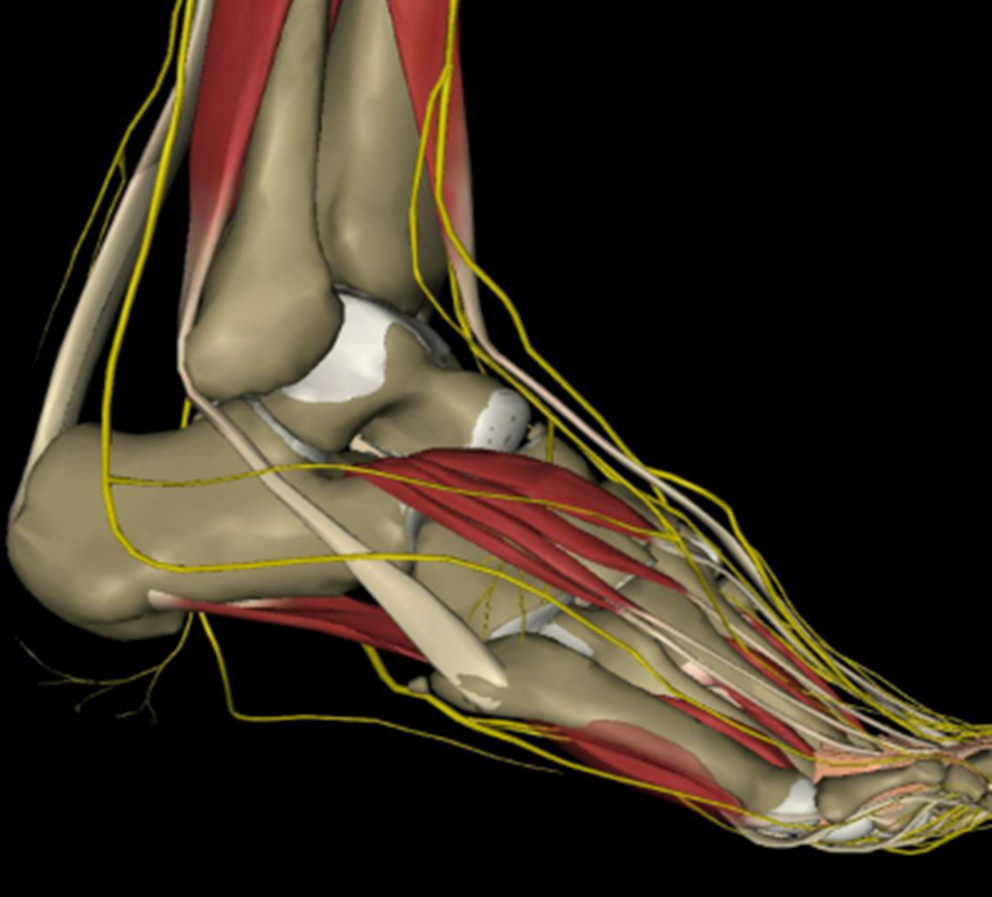

1、它是唯一有外来肌腱附着的跖骨(腓骨短肌和第三腓骨肌)。

2、它与跖腱膜有很强的韧带连接。

3、它的跖侧和外侧软组织很少。

血供情况

多支骨骺和干骺端 动脉提供基底部和粗隆部的血运,但只有一根营养动脉从内侧皮质进入骨干的近中 1/3 处为骨干提供血运,此根营养动脉只发出一个纵向的髓内分支供应骨干和粗隆部交界处血运,Jones 骨折很容易造成其损伤,所以此处很容易发生骨延迟愈合或不愈合。